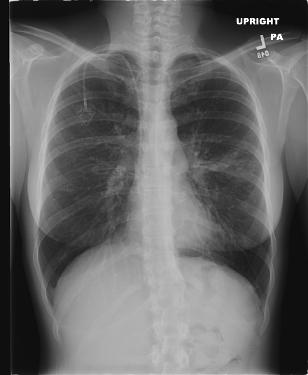

Patients are talking. Your giving us something to talk about. While hospitals are working hard to keep our medical records private, many of us in the CF community are posting details about our health and health care providers on FaceBook. We're sharing our personal xrays, CT scan images, even pictures of procedures online. Why? Because we want to compare notes with others going through the same complications. We're learning from one another. We're realizing that every CF doctor has a different opinion about what test results mean. We're realizing medicine is practiced and is not an exact science, yet we realize when we're not receiving the best available care. We're getting smarter about CF, we're learning along with you, and we're comparing you to others in your field. We're talking about you and it's affecting the reputation of your CF center and you as a professional.

In closing, in the first paragraph of this blog I posted my personal chest xray (CXR) taken a few months ago at my CF center. I posted it on FaceBook, which then prompted my Cysters and FiBros to post their CXRs as well. Within a week of me posting my CXR at least 70 of my CF friends posted their CXRs, some including PFTs next to the CXR. It was interesting to see so many CXRs from CF patients in all walks of life!